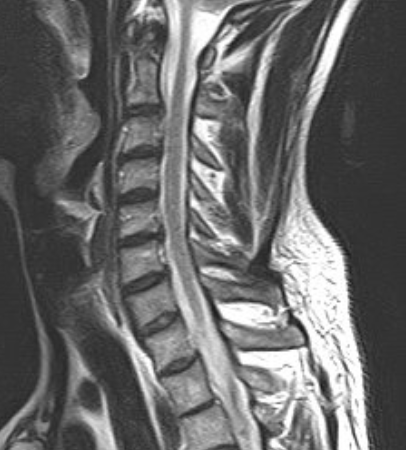

DIAGNOSI:

Ernia discale cervicale c5-c6

Risonanza magnetica cervicale pre-operatoria